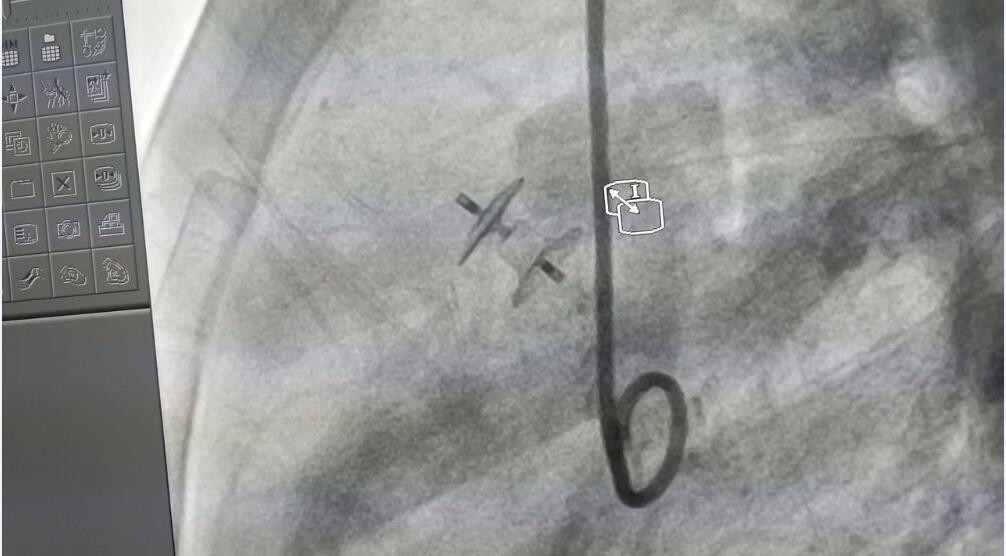

该病例为多孔膜周部室间隔缺损并伴有室缺瘤。术中测量患者左室面缺损直径为3.6 mm,右室面缺损直径为3.4mm,缺损长度为5.3mm。患儿复杂的病情使得采用传统静脉路径通过右心室侧释放变得非常困难。在Dr.Worakan的指导下,主要术者Dr.Supapon选择了彩神在线网信彩票-彩神通免费版下载-彩神8争霸vlll-彩神购彩购彩大厅-彩神软件陆立根免费版-彩神ll争霸3-彩神ll彩神8-彩神ll争霸彩票-拼搏在线彩神网网页版科技公司型号为LT-MFO-5-3的KONAR-MF™多功能封堵器,通过动脉路径释放成功。术后造影显示,患儿缺损部位封堵完全,无残余分流。

(术中超声)

(Dr.Supapon使用KONAR-MF™多功能封堵器进行手术封堵)

(术后造影)